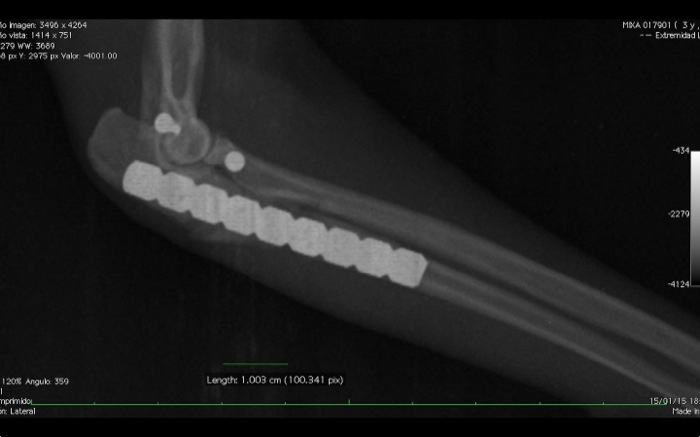

| Pruebas | Radiografía que muestra fractura múltiple de cúbito izquierdo que abarca la zona articular y separación del radio ( fractura de Monteggia). En la derecha hay una fractura de radio y cúbito diafisaria media. |

| Tratamiento | Placas de reconstrucción para tornillos de 1,5 y 2 mm. |

En este caso aplicamos tornillos de 1,5 mm que entran en lateral al cúbito. Con 2 tornillos, en cabeza de radio uno y otro en cóndilo humeral, y una sutura no absorbible (Premicrom® 2/0) tenemos una prótesis que mantendrá radio y húmero en posición fisiológica.

Ha durado mas de lo aconsejable la cirugía, 2h y 45 min. pero el resultado es estable con 2 corticales firmes por tornillo. La evolución a partir de aquí va a depender de un manejo estricto del entorno del paciente felino.